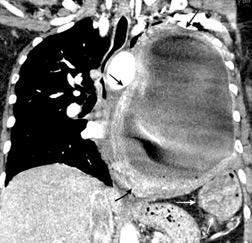

Quiste hidatídico.

Comunica con el hiato esofágico y el espacio pararrenal anterior.

Colecciones “inflamatorias” abdominales llegan al tórax vía el hiato esofágico o por vía transdiafragmática

Afectación transdiafragmática: 5,6-43,7% de quistes hepáticos. “Área desnuda” del hígado.

Panda A et al. “Straddling Across Boundaries”. Thoracoabdominal Lesions: Spectrum and Pattern Approach. Curr Probl Diagn Radiol. 2015 Área desnuda. El hígado en contacto directo con el tendón central del diafragma. Contiene el hiato de VCI.

Pedrosa I et al. Hydatid Disease: Radiologic and Pathologic Features and Complications. Radiographics 2000

Derrame pleural agudo. Migración transdiafragmática ocurre en 0,6-16% de casos. (área desnuda)